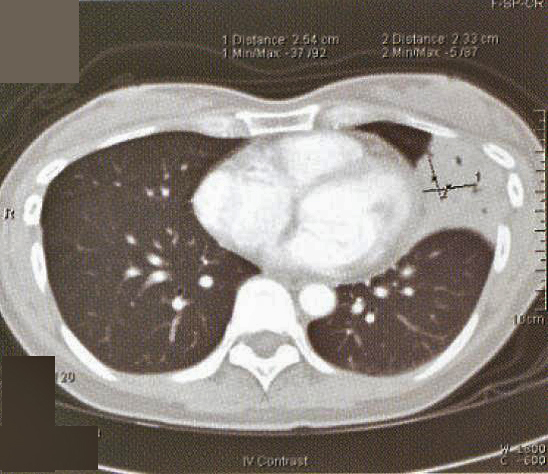

A 41-year old secretary was found having a left mid zone opacity on a routine CXR taken as part of her annual medical check-up (fig. la). This radiographic abnormality persisted after she was given a course of Azithromycin by her family physician (fig. 1b). She was a lifelong non-smoker with a past history of hyperthyroidism treated with drugs for 18 months in 1985-86 and had been euthyroid since. Two months prior to her medical check-up, she had a flu-like illness with cough and a sore throat that lasted for about a fortnight. She had been asymptomatic since apart from a slight cough occasionally. She denied any fever, weight loss, night sweat or pruritus. There was no history of taking any long-term medication or exposure to chemicals or animal pets. Clinical examination was normal and in particular, she was afebrile and not in respiratory distress. SaO2was 98% at rest whilst she was breathing room air and spirometry was normal.

Fig. 1: CXR taken at presentation (a) and 17 days later (b). Left mid zone opacity remained unchanged despite a course of Azithromycin Blood tests revealed normal CBP, ESR & routine biochemistry. Antibodies for HIV 1 & 2 were negative. Thyroid function was normal but thyroid peroxidase antibody was elevated at 81.7 IV/ml (normal <12). CT thorax showed an area of segmental consolidation in the lingular segment of left upper lobe (fig. 2a), with no abnormality detected in other parts of the lungs, mediastinum or body structures. Bronchoscopy revealed nothing abnormal and bronchial washings grew alpha streptococcus but were negative for AFB smear, M tuberculosis DNA or malignant cells. She developed a cough after the bronchoscopy and responded to a course of levofloxacin.